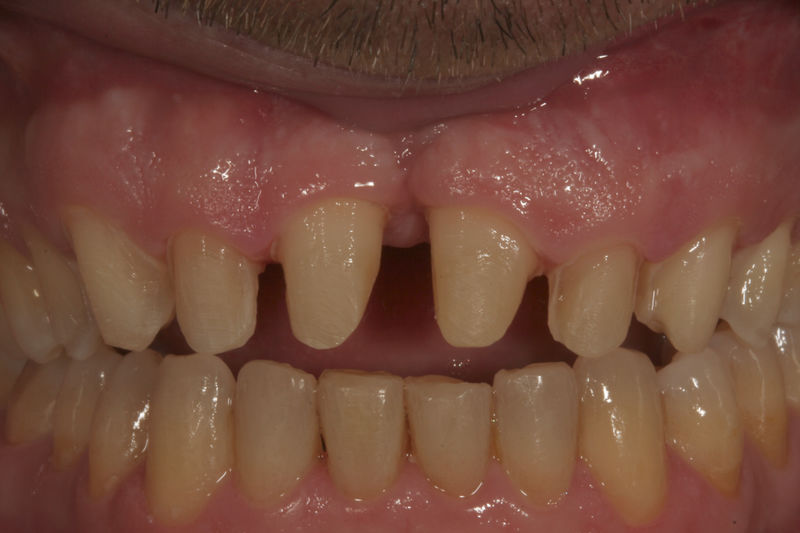

Las prótesis dentales son aparatos o dispositivos que se utilizan para reemplazar los dientes ausentes y las estructuras orales relacionadas.

Restauraciones fabricadas en el laboratorio con materiales estéticos, los cuales se usan para reemplazar dientes ausentes usando coronas como soporte. Para poder enviar el caso al laboratorio se toman impresiones utilizando materiales de impresión o técnicas modernas digitales.

Implantes, ortodoncia y coronas.